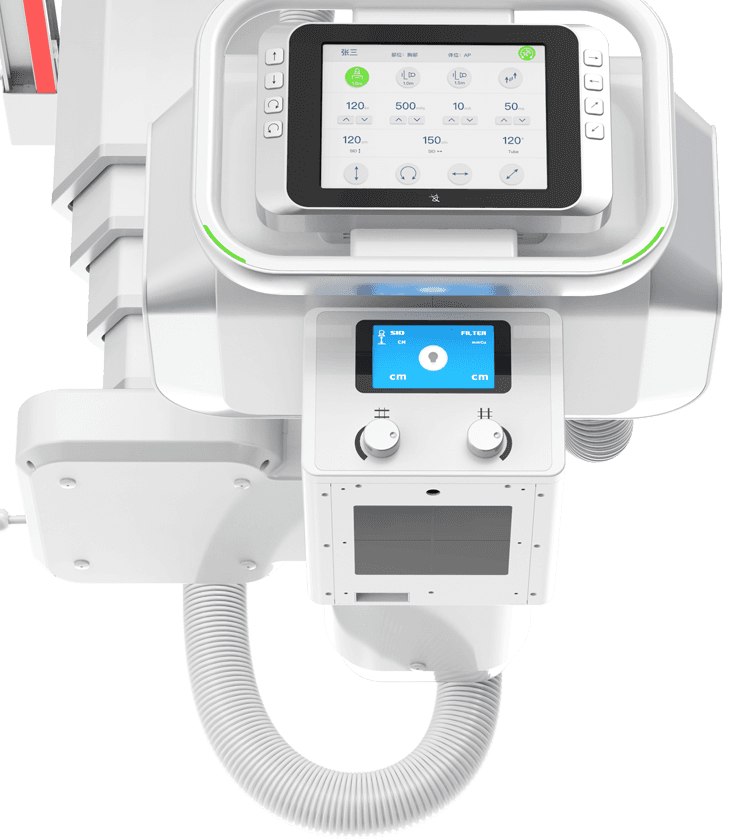

¶а№¦ДЬРьµхКЅ»ъРµФЛ¶ЇЈ¬И«ЖЅєвОИ¶ЁРФЙијЖЈ¬4DК®ЦбБЄ¶ЇјјКхЈ¬»ъјЬФЛ¶ЇЧФИзЖЅОИЈ¬

ЕдєПµз¶ЇЙэЅµґІј°¶а№¦ДЬБўКЅЙгУ°јЬЈ¬ЗбЛЙВъЧгБЩґІИ«МеО»ЙгУ°РиЗуЎЈ

Зт№ЬОеПтКЦЧФТ»МеФЛ¶Ї

ІЙУГКЦ¶ЇУлµз¶ЇТ»Ме»ЇЙијЖЈ¬ІўѕЯ±ёёРУ¦Зэ¶Ї№¦ДЬЈ¬

Т»јьЅвЛшјґїЙЗбЛЙІЩїШЗт№ЬµДИ«ПтФЛ¶ЇЎЈ -

МЅІвЖчЎўЗт№ЬЛ«ПтЧФ¶ЇёъЧЩ

МЅІвЖчУлЗт№ЬїЙКµПЦЛ«ПтЧФ¶ЇёъЧЩЈ¬

БўОФО»ёЯѕ«¶ИКµК±Н¬ІЅЈ¬ґу·щМбёЯБЩґІјмІйР§ВКЎЈ -